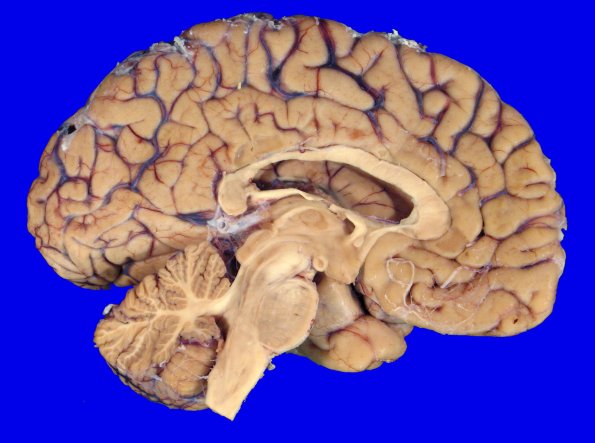

1A2 NCL (Case 1) gross 3

There was minimal apparent atrophy of the cerebral hemispheres.